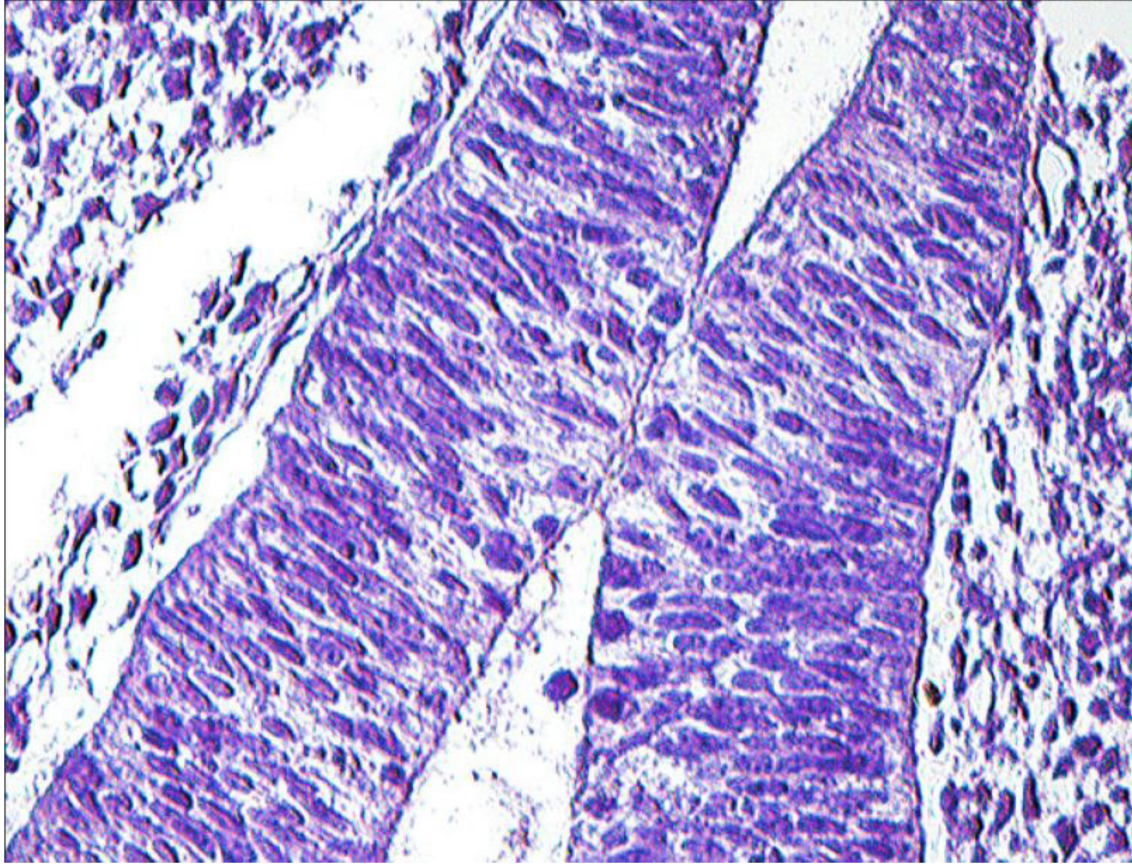

Компоненты жаберного аппарата участвуют в построении глоточной кишки и ее производных. Диссоциация хорды на уровне орофарингеальной мембраны позволило сформироваться стомодеальному карману и карману Ратке – источнику развития аденогипофиза (рис. 2).

Рис. 2. Эмбрион человека. Биологический возраст 30–32 суток: 1 – устье кармана Ратке; 2 – карман Сесселя; 3 – глоточная кишка; 4 – стенка промежуточного мозгового пузыря. Фиксация: 10%-й нейтральный формалин. Окраска: ШИК-метод по Мак-Манусу. 7 × 40